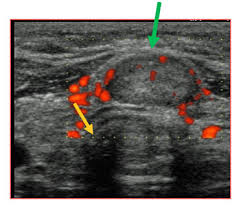

A lump which appears on the neck could be a warning sign. Swelling in the neck though not all enlargement of the neck area is cancerous (such as goiter, a symptom of hypothyroidism), an ultrasound of the thyroid can confirm if a nodule is in fact benign. Most don't notice their thyroid gland until something is wrong and they need to be examined by a doctor. Doctors also use a cancer's stage when talking about survival statistics. Thyroid cancer is a rare type of cancer that affects the thyroid gland.